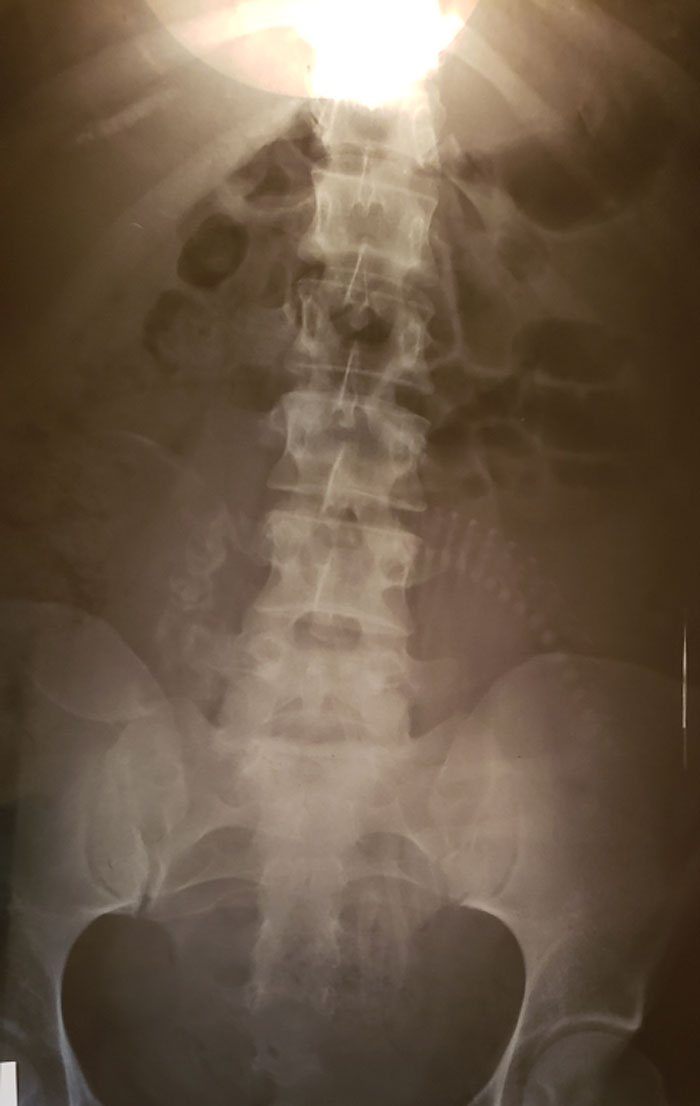

Dads Leg Xray

Advanced Rheumatoid Arthritis

My daughter was diagnosed with RA when she was 13. She is 29 now and has had three surgeries to improve her joints to help her be able to walk. Her toes looked much like this X-ray. This is a horrible illness that is invisible until it is at this point. The pain that these patients deal with every day is heartbreaking. People still give her dirty looks when she uses a handicap parking space. Imagine if your toes looked like this...don't you think you would want to walk as little as possible?